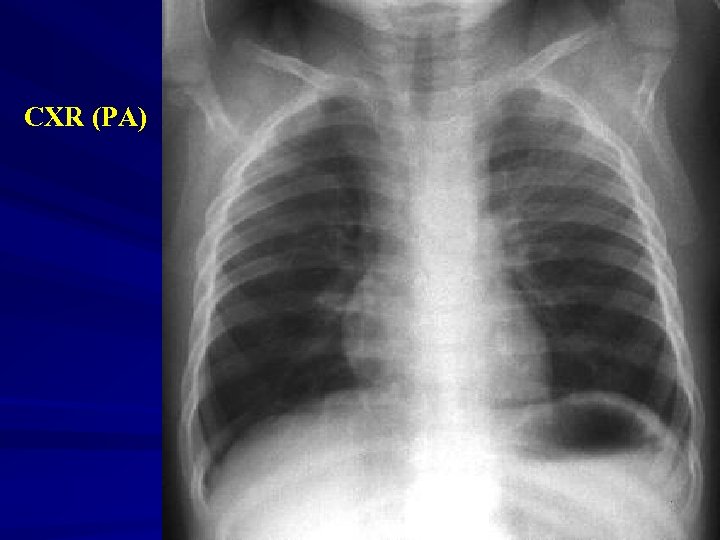

CXR (PA)

Next? Expiratory CXR

Investigations Xrays Ø Lateral neck Ø Chest – inspiratory, expiratory, decubitus views Expiratory views Overinflation (partial obstruction with inspiratory flow) Volume loss with mediastinal shift towards obstructed side (partial obstruction with expiratory flow) Atelectasis (complete obstruction)

Decubitus views Normal Smaller volumes and elevated diaphragm on side down Abnormal Hyperinflation or “normal” volumes in decub position If suspected … Need a bronchoscope to rule out or remove Foreign Body